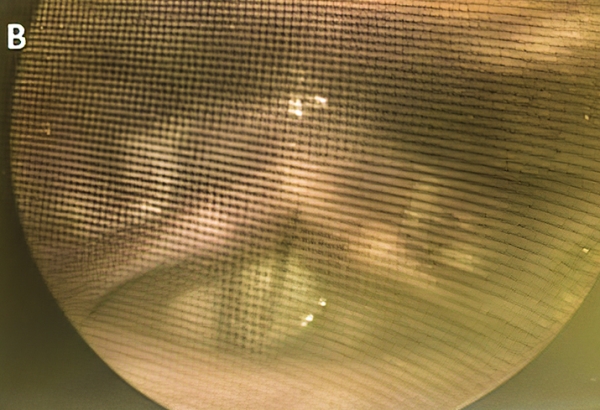

После лечения при ларингоскопическом исследовании визуализировалось полное смыкание голосовых складок у всех пациентов с недостаточностью голосового аппарата, а также имело место уменьшение передне-заднего и/или латерального сдавления вестибулярного отдела гортани (см. рис. 1).

Рисунок 1. Пациент с недостаточностью голосового аппарата до (А) и через 1 месяц после лечения (В).